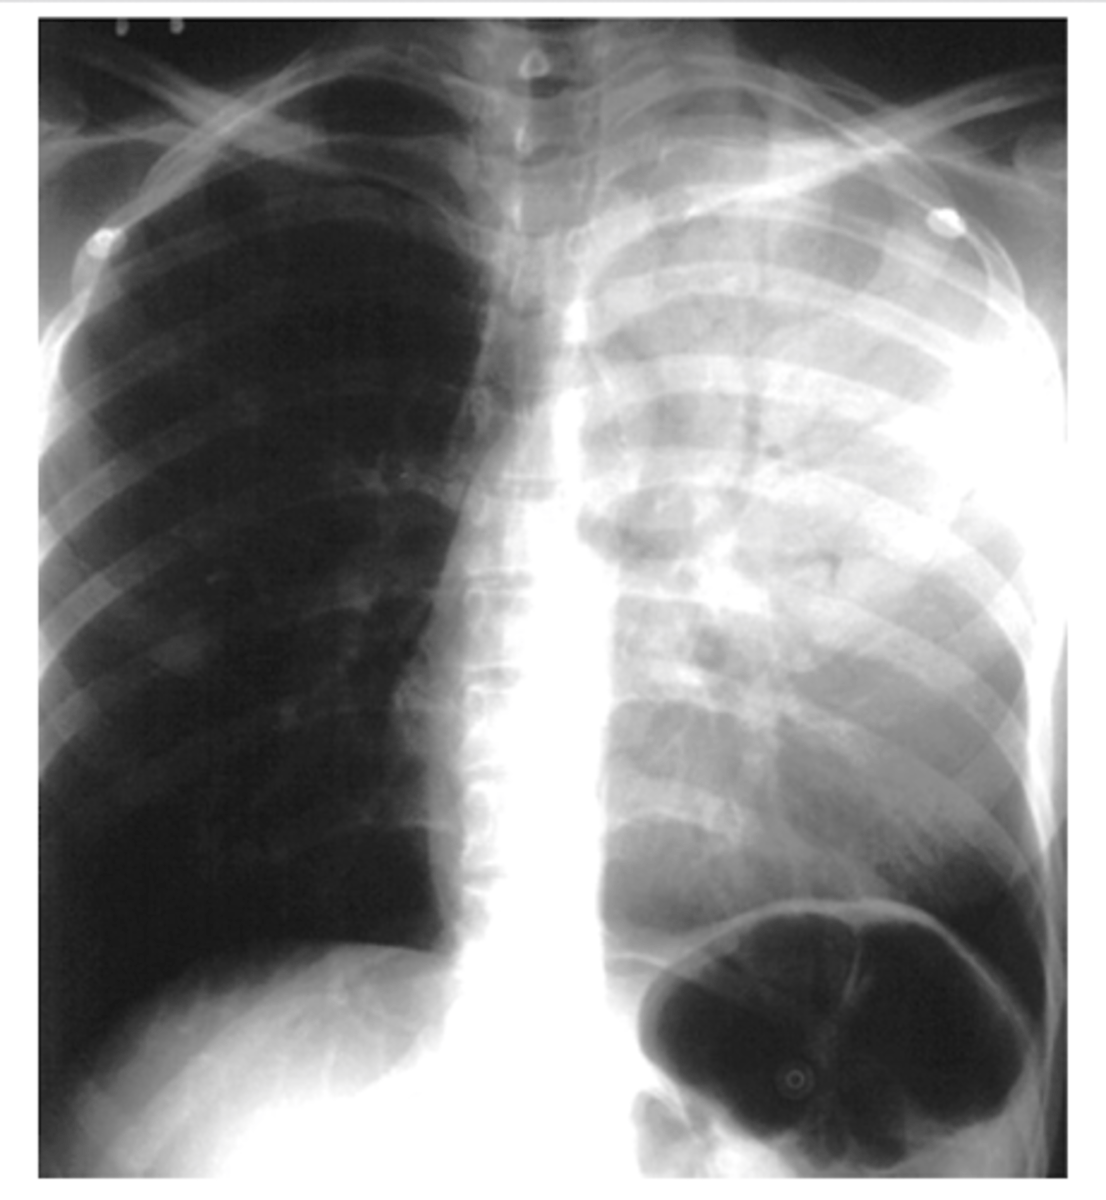

ARDS x-ray appearance

"white out appearance" sometimes with sparing of costophrenic angles

<p>"white out appearance" sometimes with sparing of costophrenic angles</p>